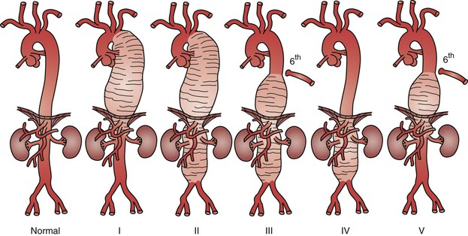

Διαφορετικά είδη ανευρυσμάτων

Η μεγάλη εξέλιξη των ενδαγγειακών μοσχευμάτων έχει καταστήσει δυνατή την αντιμετώπιση του συνόλου σχεδόν των διαφορετικών αορτικών ανευρυσμάτων. Ανευρύσματα της θωρακικής αορτής, θωρακοκοιλιακά ανευρύσματα και κοιλιακά ανευρύσματα που περιλαμβάνουν τις σπλαχνικές αρτηρίες, αποκαθίστανται με ενδομοσχεύματα ειδικής παραγγελίας. Μία αξονική τομογραφία χρησιμοποιείται για τον σχεδιασμό εξειδικευμένου μοσχεύματος με τη βοήθεια ειδικού λογισμικού, σύμφωνα με την μορφή και την ανατομία της αορτής του κάθε ασθενούς. Το μόσχευμα αυτό κατασκευάζεται και τοποθετείται στο εσωτερικό της αορτής με επέμβαση που πραγματοποιείται στην υβριδική αίθουσα